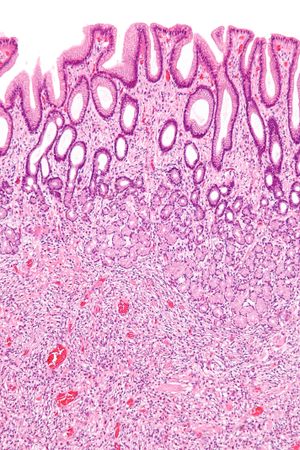

| 과형성 용종 | 대장 (별도로 명시되지 않는 한) | 톱니 모양의 분지되지 않은 샘 | 용종이 100개 이상인 경우 | ![]() | 톱니 용종증 증후군 |

| 과형성 용종 | 대장 (별도로 명시되지 않는 한) | 톱니 모양의 분지되지 않은 샘 | 용종이 100개 이상인 경우 | 톱니 용종증 증후군 | |